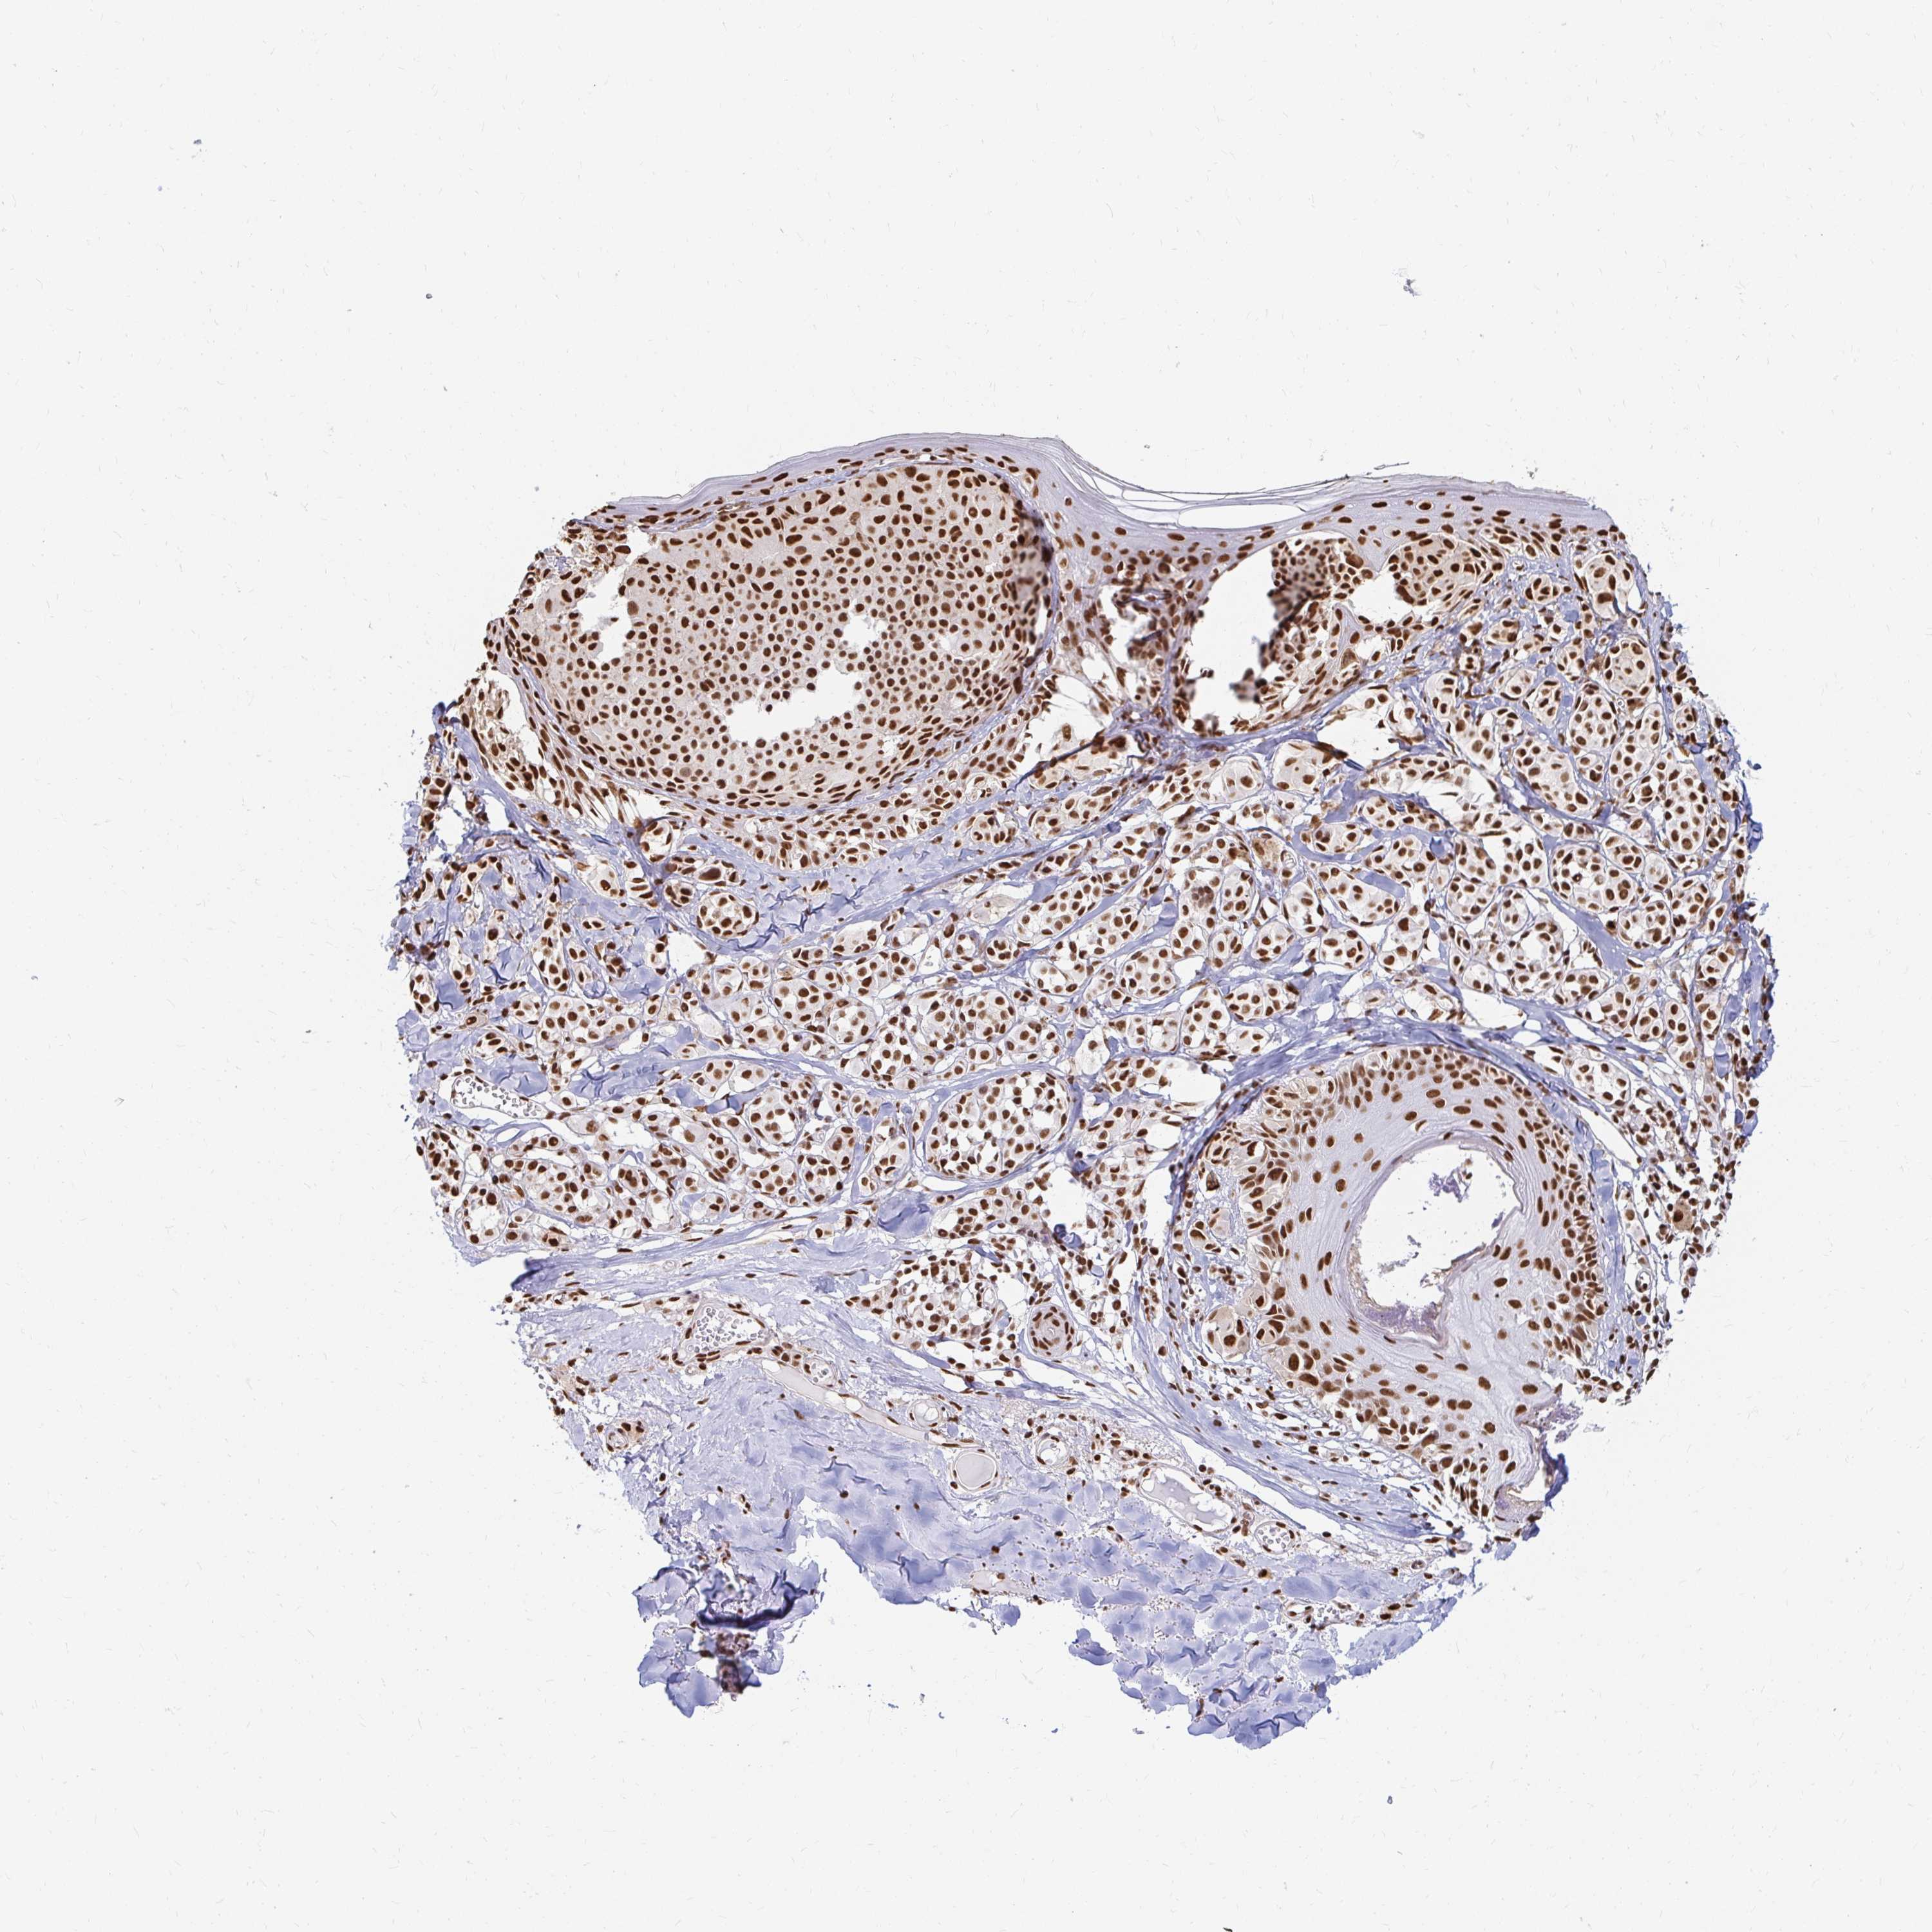

MELANOMA - Protein expressioni

A mouse-over function shows sample information and annotation data. Click on an image to view it in a full screen mode. Samples can be filtered based on level of antibody staining by selecting one or several of the following categories: high, medium, low and not detected. The assay and annotation is described here.

Note that samples used for immunohistochemistry by the Human Protein Atlas do not correspond to samples in the TCGA dataset.

Antibody stainingi

Antibody staining in the annotated cell types in the current human tissue is reported as not detected, low, medium, or high, based on conventional immunohistochemistry profiling in selected tissues. This score is based on the combination of the staining intensity and fraction of stained cells.

Each image is clickable and will lead to virtual microscopy that enables deeper exploration of all samples and also displays staining intensity scores, fraction scores and subcellular localization as well as patient and tissue information for each sample.

Antibody HPA041057

Antibody HPA058707

Antibody CAB011532

Staining

High

Medium

Low

Not detected

Intensity

Strong

Moderate

Weak

Negative

Quantity

>75%

75%-25%

<25%

None

Location

Nuclear

Cytoplasmic/membranous

Cytoplasmic/membranous,nuclear

Malignant melanoma, NOS

Malignant melanoma, Metastatic site